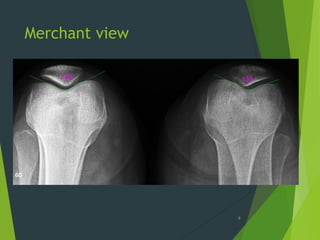

Merchant view

6